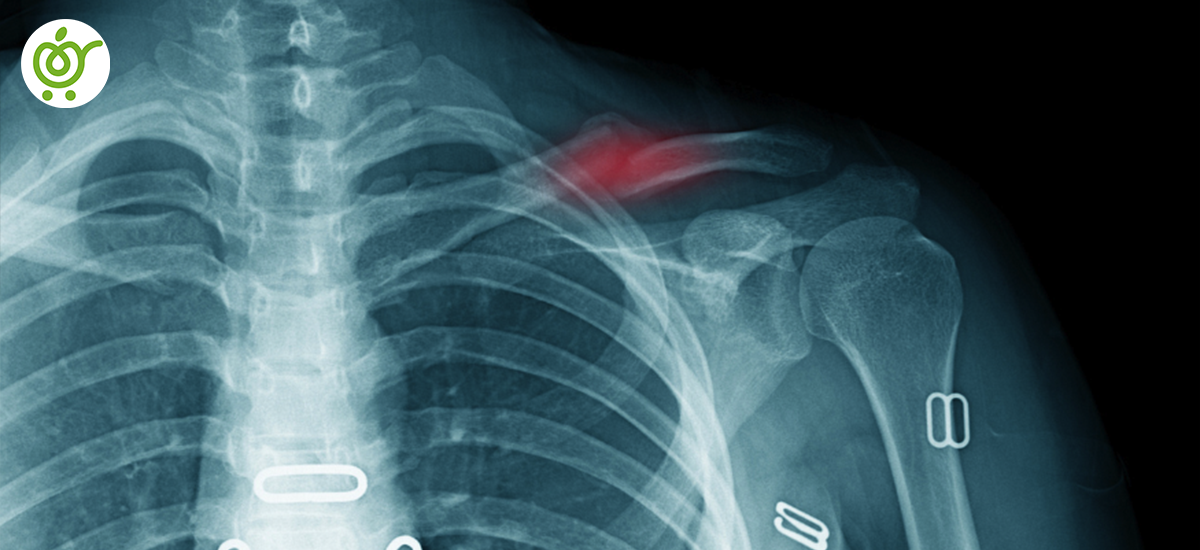

درمان شکستگی ترقوه

شکستگی استخوان ترقوه یکی از شکستگیهای دردناک بدن است و به دلیل موقعیت خاص این استخوان، مراقبتهای ویژهای را میطلبد. معمولاً در این نوع شکستگی، قطعات شکستهشده به اندازهای جابهجا نمیشوند که نیاز به مداخلهی جراحی باشد و میتوان با یک جا اندازی ساده و بانداژ مناسب، استخوان را در جای خود تثبیت کرد. با این حال، در مواردی که شکستگی با جابهجایی زیاد قطعات همراه باشد، خطر آسیب به عروق و اعصاب افزایش مییابد.

انواع شکستگی ترقوه

شکستگی استخوان ترقوه به سه نوع اصلی تقسیم میشود که هر یک از آنها بر اساس محل شکستگی در استخوان ترقوه مشخص میگردد:

1. شکستگی یک سوم خارجی: این نوع شکستگی حدود 10 درصد از شکستگیهای استخوان ترقوه را تشکیل میدهد و در بخش خارجی استخوان رخ میدهد. شدت این نوع شکستگی به میزان آسیبی که به رباطهای متصل کننده ترقوه به استخوان کتف وارد میشود بستگی دارد. در صورتی که این رباط آسیب ببیند، احتمال جا به جایی قطعات استخوان و شدت شکستگی افزایش مییابد. برای درمان، هم میتوان از روشهای جراحی و هم غیرجراحی استفاده کرد.

2. شکستگی یک سوم میانی: این نوع شکستگی شایعترین نوع شکستگی ترقوه است و بیش از 80 درصد موارد را شامل میشود. در بیشتر موارد، درمان این نوع شکستگی با جا انداختن استخوان و بانداژ محل شکستگی انجام میشود. اما اگر شکستگی بسیار شدید باشد، ممکن است نیاز به استفاده از پروتزهای فلزی برای ثابت کردن استخوان باشد.

3. شکستگی یک سوم داخلی: این نوع شکستگی کمتر از 10 درصد از شکستگیهای استخوان ترقوه را شامل میشود و در بخش داخلی استخوان رخ میدهد. به دلیل حمایت خوب رباطهای متصل کننده استخوان ترقوه به جناغ سینه، این نوع شکستگیها معمولاً شدید نیستند و بیشتر با روشهای غیرجراحی درمان میشوند.